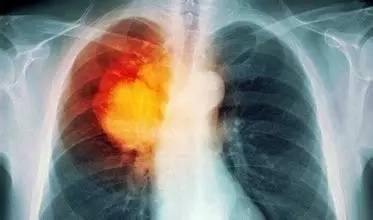

抗癌防癌知识—肺癌

三、肺癌的诊断

1.X线检查:是诊断肺癌的主要手段。中心型肺癌的X线表现,在早期可以无异常征象。